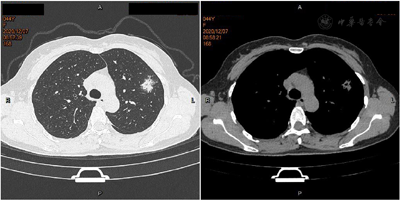

患者,女性,44岁,主因"反复发热6 d"于2020年12月11日入院。患者于6 d前受凉后出现发热,体温最高39.2℃,热型无规律,无畏寒,无寒战,无汗,无咳嗽,无咽痛,无鼻塞、流涕,无味觉、嗅觉减退,无结膜炎,无肌肉酸痛,无乏力,无腹泻,无皮疹。自服退热药(具体药物不详)后体温退至正常,转日体温再次升高,2020年12月7日就诊于我院发热门诊,查血常规+CRP:WBC 6.6×109/L,Neu% 78.2%,Lym% 14.3%,CRP 17.7 mg/L,新冠病毒核酸检测、新冠病毒抗体(IgG+IgM)阴性,胸部CT平扫考虑左肺上叶感染(图1),予头孢克肟口服治疗,仍反复发热。2020年12月11日再次就诊于我院发热门诊,查血常规+CRP:WBC 4.19×109/L,Neu% 73.1%,Lym% 19.3%,CRP 87.7 mg/L,胸部CT平扫:左肺上叶片状磨玻璃状阴影,较前明显增大,考虑炎性病变(图2),以"肺部感染"收入院。刻下症:发热,热型无规律,纳差,眠可,二便调。既往体健,否认慢性病史。末次月经2020年12月3日。